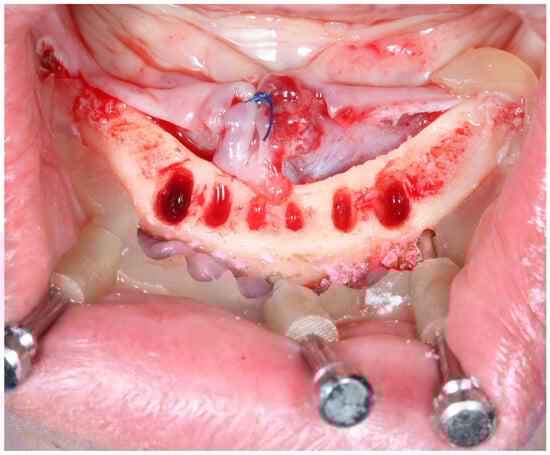

All surgeries were performed by surgeons of equivalent skill levels using a computer navigation drill kit (Magellan, CMC Equipment, Milan, Italy). Following local anesthesia, the surgical guide was positioned and secured with 3–4 bone fixation pins. A flapless approach was adopted whenever possible; otherwise, a minimal mucoperiosteal flap was elevated. Osteotomies were prepared using the guided drills, and Rootform implants (Pro-Trate, Warszawa, Poland) with diameters ranging from 3.8 mm to 5.5 mm were placed (Figure 3, Figure 4 and Figure 5). A total of 140 implants were inserted (Table 1). Implants were placed with a minimum insertion torque of 35 Ncm and were immediately loaded with a provisional prosthesis.

Figure 5. Clinical application of osteotomy part of the bone supported guide.